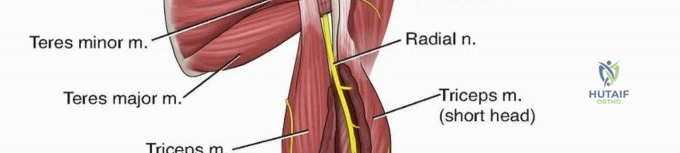

The radial nerve is the most critical anatomical structure at risk during both the initial injury and subsequent surgical approaches to the humerus. The nerve, accompanied by the profunda brachii artery, exits the axilla and passes through the triangular interval. This interval is bordered superiorly by the teres major, medially by the long head of the triceps, and laterally by the humeral shaft.

From the triangular interval, the radial nerve transverses from medial to lateral along the posterior aspect of the humeral shaft within the spiral groove. It pierces the lateral intermuscular septum approximately 10 to 12 centimeters proximal to the lateral epicondyle to enter the anterior compartment of the arm. Distally, the nerve travels in the anatomic interval between the brachialis muscle medially and the brachioradialis muscle laterally. This specific interval is the foundation of the distal anterolateral approach to the humerus.